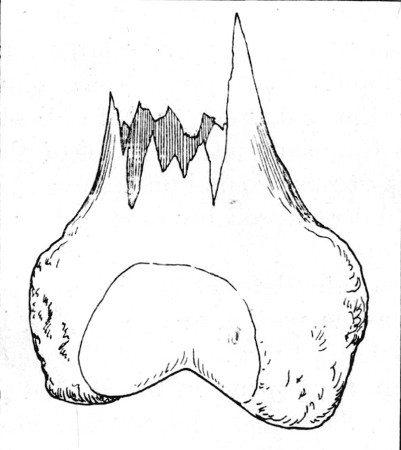

53. Gutter Fracture of Head of Humerus178

63. Fragment of Inner Table Displaced from Opening seen in Fig. 62 253